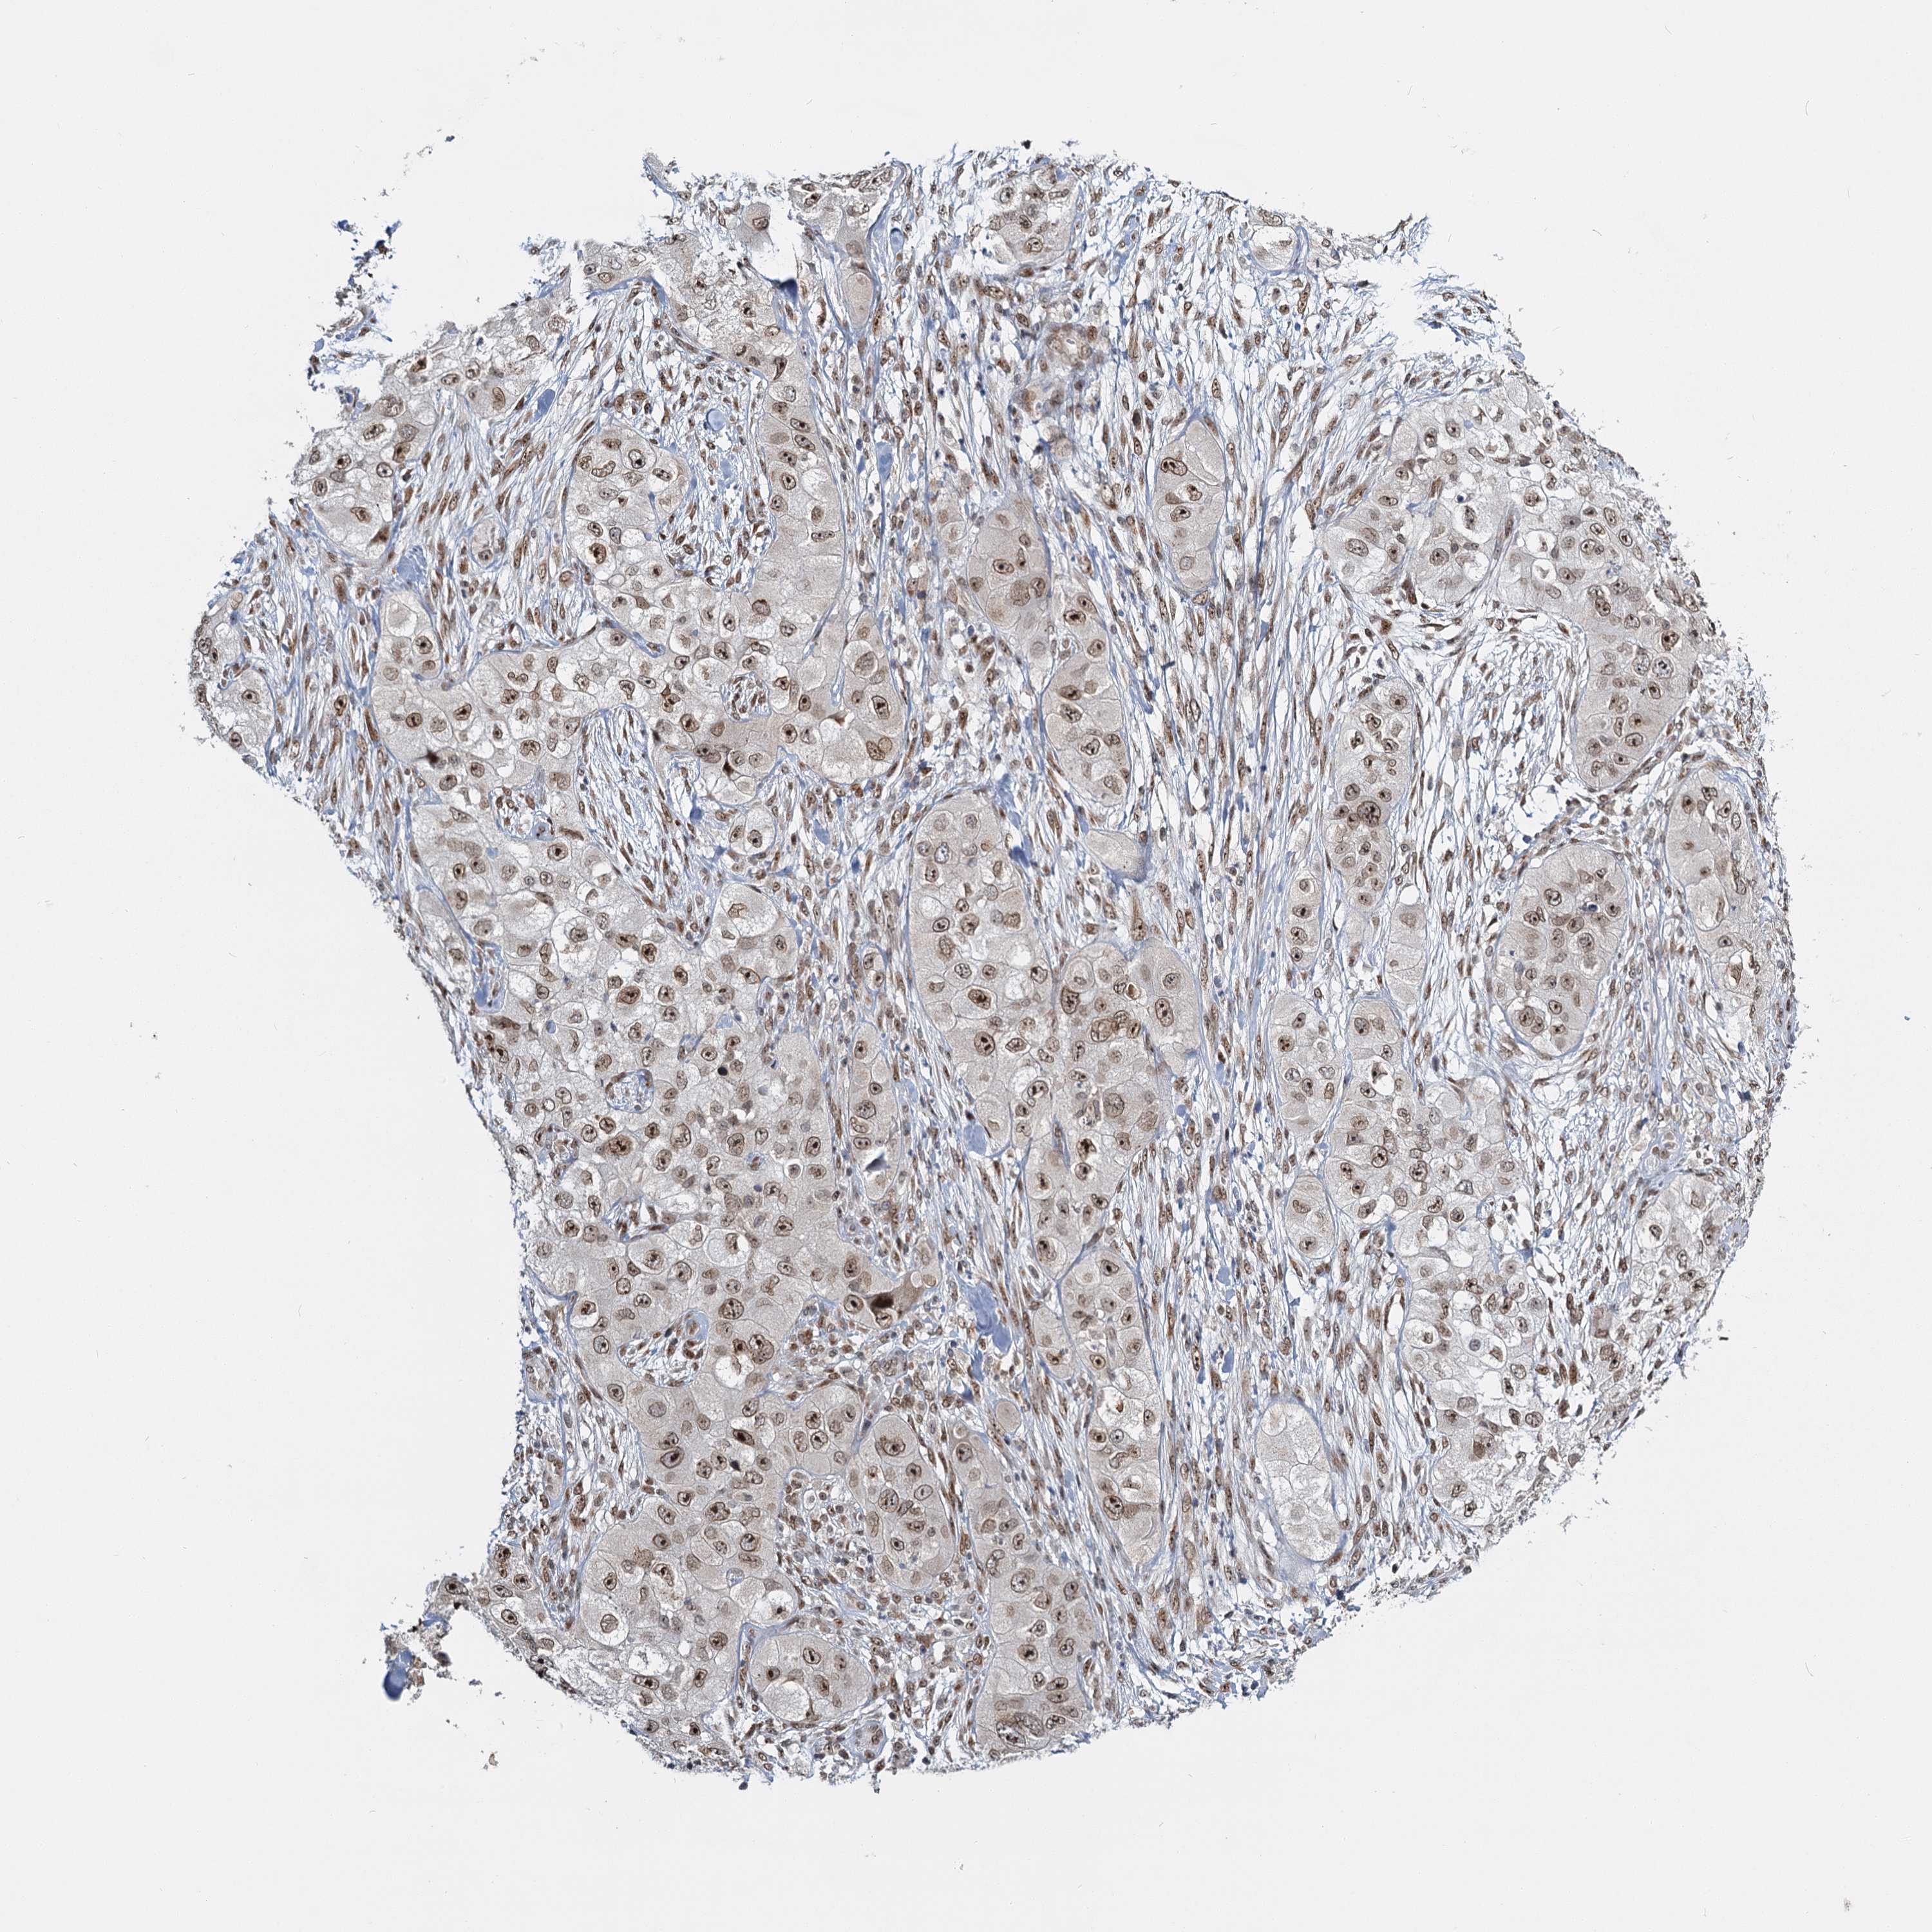

Basal cell and squamous cell cancer

SKIN CANCER - Protein expressioni

A mouse-over function shows sample information and annotation data. Click on an image to view it in a full screen mode. Samples can be filtered based on level of antibody staining by selecting one or several of the following categories: high, medium, low and not detected. The assay and annotation is described here.

Each image is clickable and will lead to virtual microscopy that enables deeper exploration of all samples and also displays staining intensity scores, fraction scores and subcellular localization as well as patient and tissue information for each sample.

Antibody HPA035437

Staining

High

Medium

Low

Not detected

Intensity

Strong

Moderate

Weak

Negative

Quantity

>75%

75%-25%

<25%

None

Location

Nuclear

Cytoplasmic/membranous

Cytoplasmic/membranous,nuclear

Basal cell carcinoma